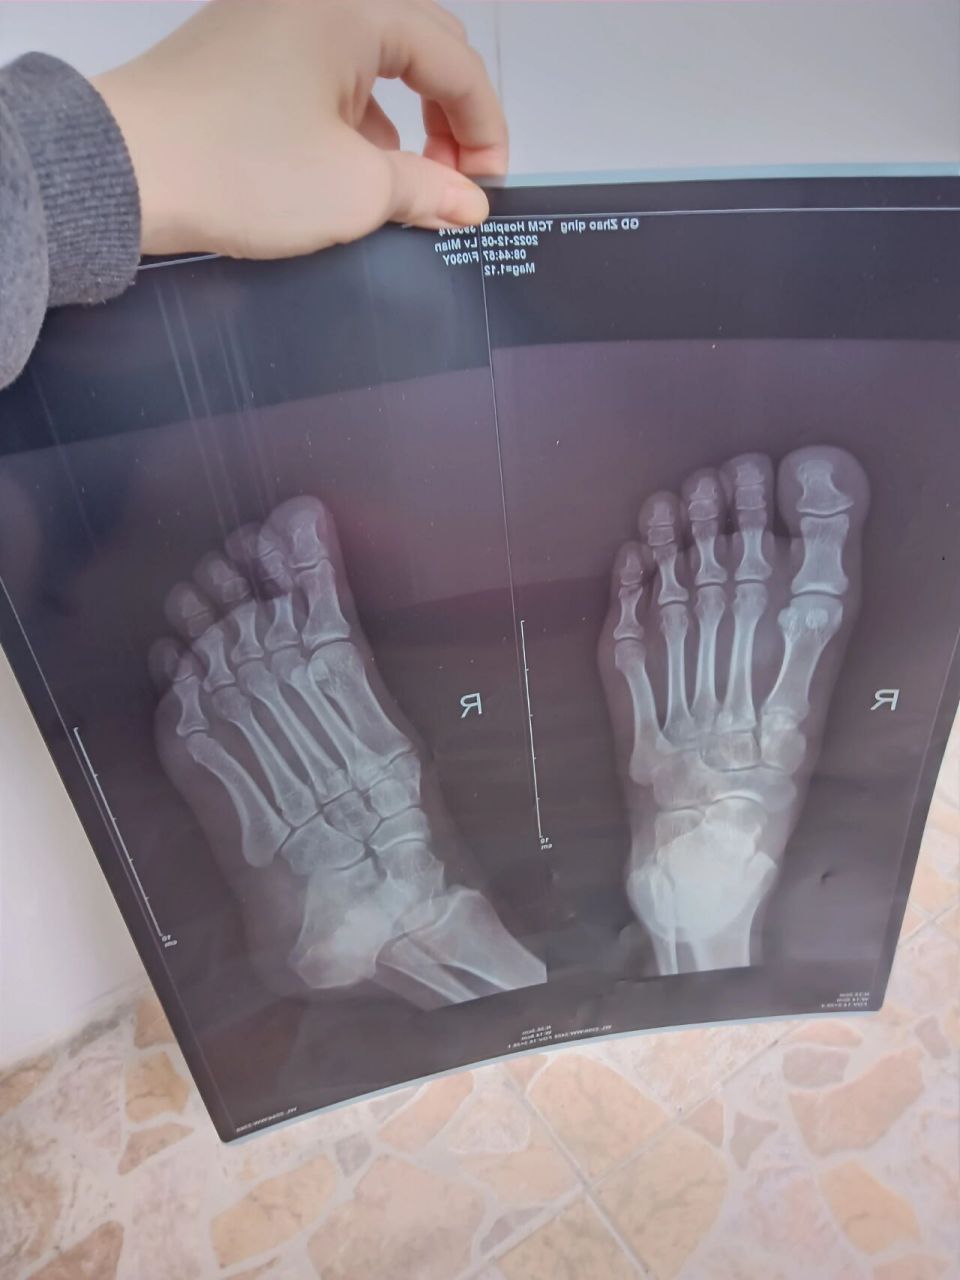

右足骨折图一第一次拍片图二三是第二次复诊 x光拍片不会看,有的骨又

脚掌骨折康复记录之第一周 1月4日骨折,诊断结果是第二第四跖骨两处均

图片尺寸960x1280